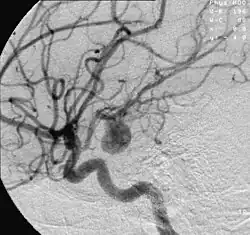

![]() | |

| Angiography of an aneurysm in a brain artery. The aneurysm is the large bulge in the center of the image. | |